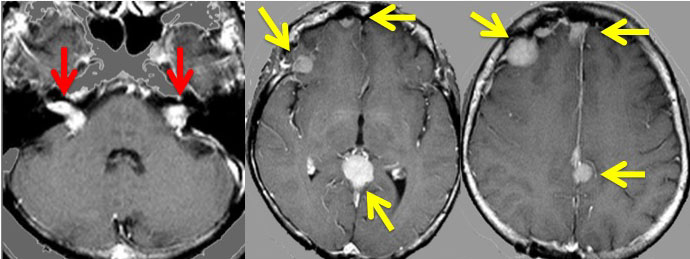

中心となるのは神経鞘腫と髄膜腫です。下のMRIは典型的な両側聴神経腫瘍と呼ばれる画像です。両側の内耳道から腫瘍(黒く見えるもの)が突出して,脳幹部を強く圧迫しているために脳幹部が縦長に変形してしまっています。この様にひどい脳幹部変形でもほとんど症状が無く暮らしていた患者さんです。赤い矢印で示すのは横静脈洞内から突出している髄膜腫です。

小脳橋角部腫瘍あるいは聴神経腫瘍と呼ばれるので,左右に一つずつの腫瘍かと思ってしまうのですが,実は違います。この患者さんでは,右側の小脳橋角部腫瘍は,三叉神経鞘腫,前庭神経鞘腫,蝸牛神経鞘腫,顔面神経鞘腫,迷走神経鞘腫,舌咽神経鞘腫,舌下神経鞘腫がすべて一塊になったものでした。ですからこの小脳橋角部腫瘍を摘出しようとすれば,上に書いた神経の麻痺は手術合併症として全部出現する可能性があります。

脳と腰部のガドリニウム増強MRIです。腫瘍は白く見えるようにしてあります。黄色の矢印で示した以外にも無数の神経鞘腫があります。

NF-2の多発性髄膜腫

赤の矢印が,両側の聴神経腫瘍です。黄色の矢印は, 多発性の髄膜腫です。蝶形骨縁髄膜腫,穹隆部髄膜腫,大脳鎌髄膜腫,大脳鎌テント接合部髄膜腫などいっぱいあります。これらは基本的に経過観察しますが,とても目立って大きくなるものがあれば摘出します。摘出には注意が必要で,近い将来また手術になるかもしれないので,次回の手術もできるように工夫して開頭手術しなければなりません。でないと,次の手術での合併症が増えます。また一回の開頭で近傍の硬膜や腫瘍を可能な限り摘出してしまうことも大切です。でないと,限りなく手術を繰り返すことになります。